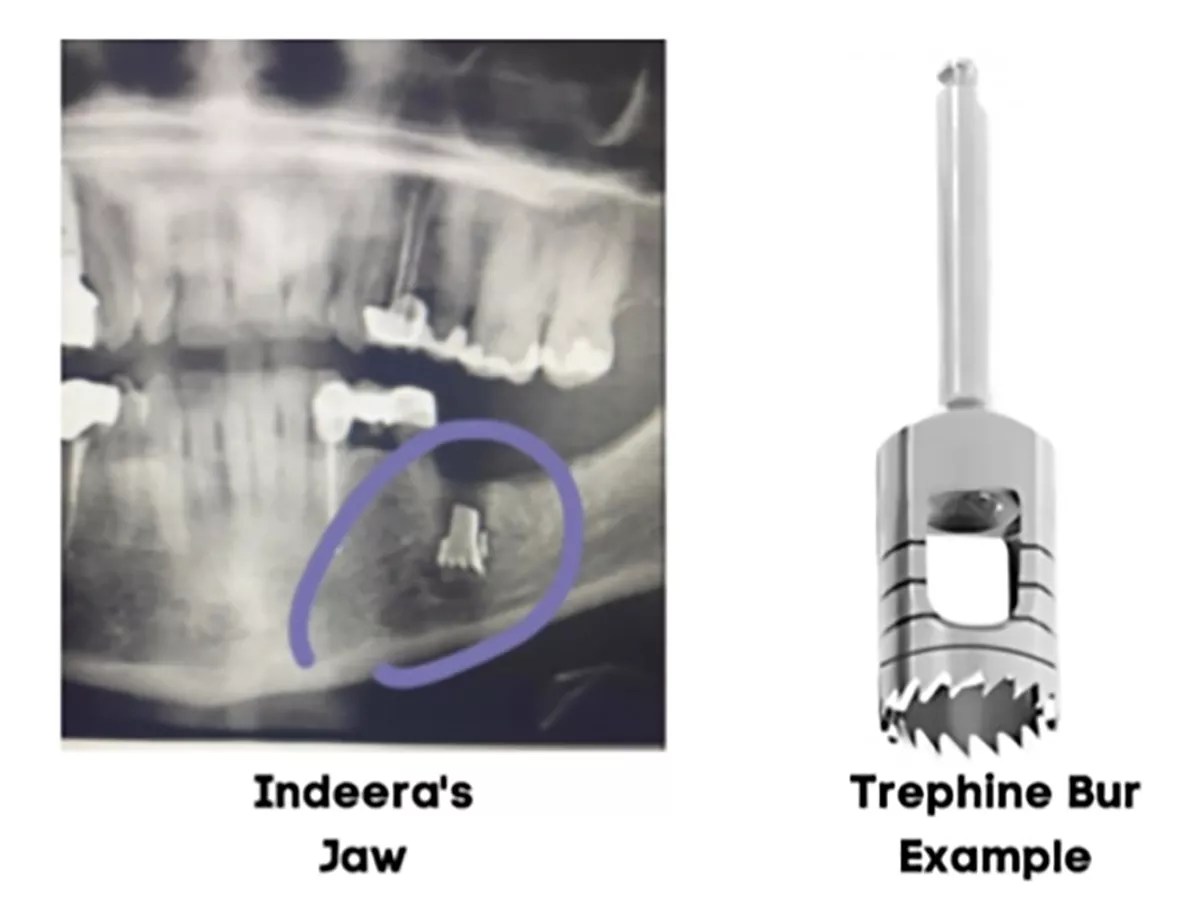

The surgery required Scott to use a drill bit called a trephine bur to remove the two faulty implants.

Usually, the stainless steel trephine bur is sunk over the failed implant and drilled into the jawbone. This creates a hole that allows the implant to be removed. Material is then grafted over the hole to prevent bone loss and preserve the area for future procedures.

When Musa returned in June, Scott did an X-ray on her jaw to see if it was ready for the new implants. The X-rays showed a dense metallic object in Musa’s jaw. Scott revealed that it was a broken piece of a drill bit he used during the surgery. He told Musa not to worry and likened “this conduct to leaving metal bullet fragments in a patient’s body,” according to the lawsuit.